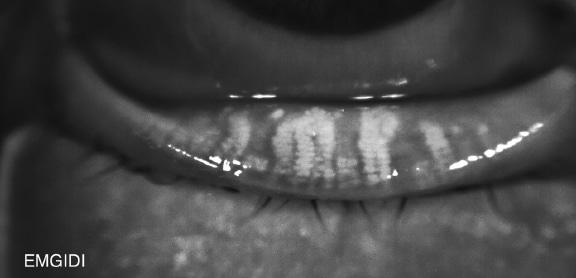

Stades d'atrophie des glandes de Meibomius

Stade 1

Moins de 33% des glandes atrophiées

–Peu ou pas de dilatations